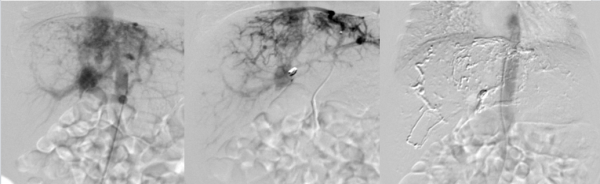

左图:腹主动脉造影显示肝内多发复杂动静脉瘘及动门脉瘘;中图:膈动脉造影膈动脉参与肝内复杂动静脉瘘;右图:术后造影显示肝内多发复杂动静脉畸形成功栓塞。

手术在麻醉科、手术室与新生儿科的全程监护下进行。放射介入团队经股动脉穿刺入路,造影显示肝内多支畸形血管弥漫分布,膈动脉亦参与形成复杂的肝动静脉瘘及肝动脉-门静脉瘘,病情较预期更为复杂。手术团队使用微导管超选择性插至瘘口近端,先以可控弹簧圈栓塞减缓血流,再以生物胶进行精准栓塞,在彻底处理畸形血管的同时,尽可能保留正常肝组织血供。术中面临血管细微、操作空间有限、循环不稳定等多重挑战,团队凭借精湛技术顺利完成栓塞,术后造影证实异常瘘口已完全闭塞。历时两个小时,手术顺利结束,取得成功。